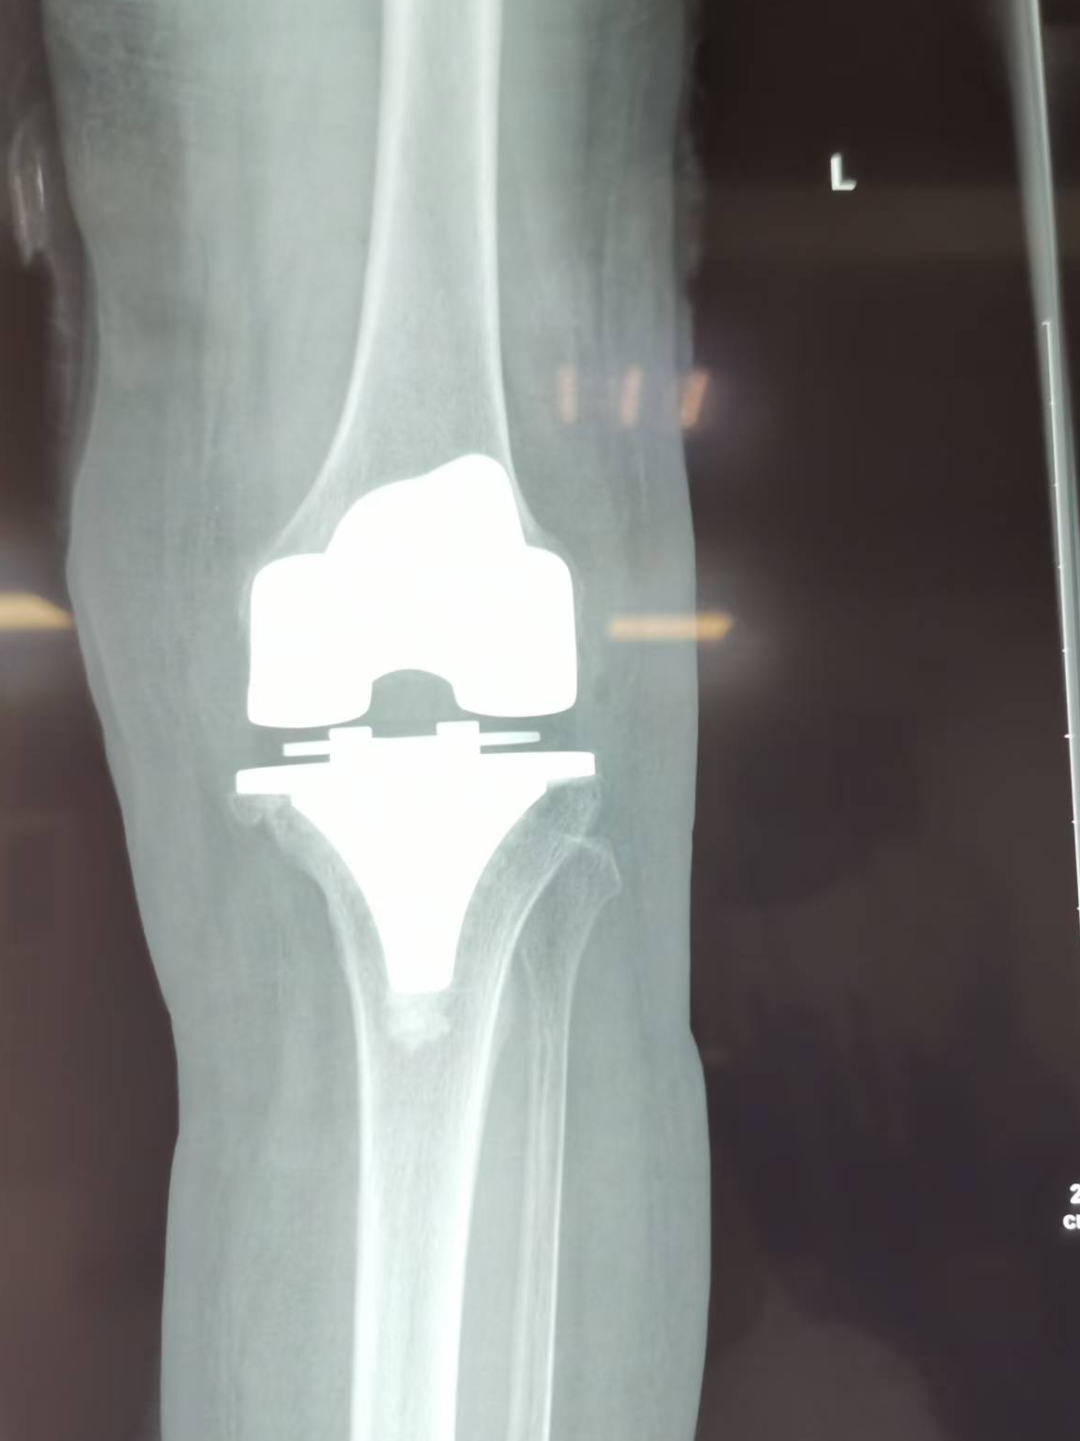

▲莫阿姨术后X线片

术后6小时,莫阿姨麻醉醒来后已能在助行器辅助下下床行走,术后1周便可丢弃助行器行走自如,1月后关节功能恢复良好,生活恢复正常。在莫阿姨的充分信任和该院骨伤科精湛技术的共同努力下,莫阿姨重新收获了一个生活质量美好的晚年。